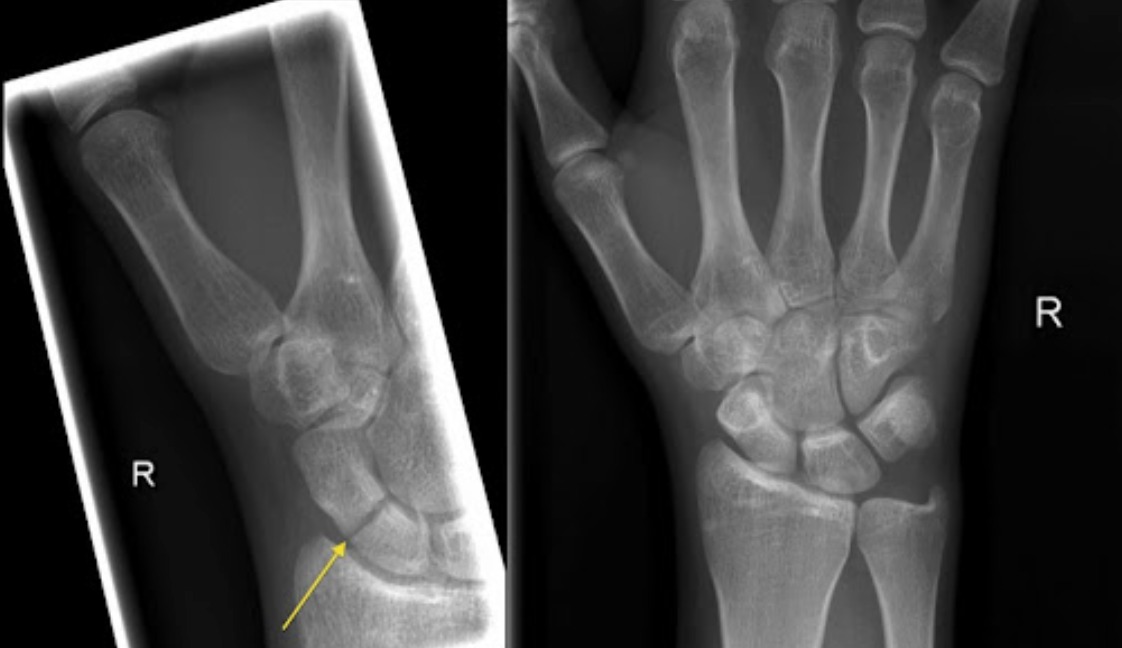

• The diagnosis is frequently missed on initial X-ray: plain films miss approximately 20% of acute scaphoid fractures — do not rely on a negative X-ray to exclude the diagnosis in a patient with snuffbox tenderness

• Initial X-ray: AP, lateral, and scaphoid views (scaphoid oblique). Sensitivity only ~70% acutely — a negative X-ray does not exclude fracture.